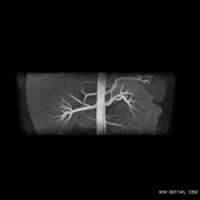

造影剤を使用しない腹部血管検査